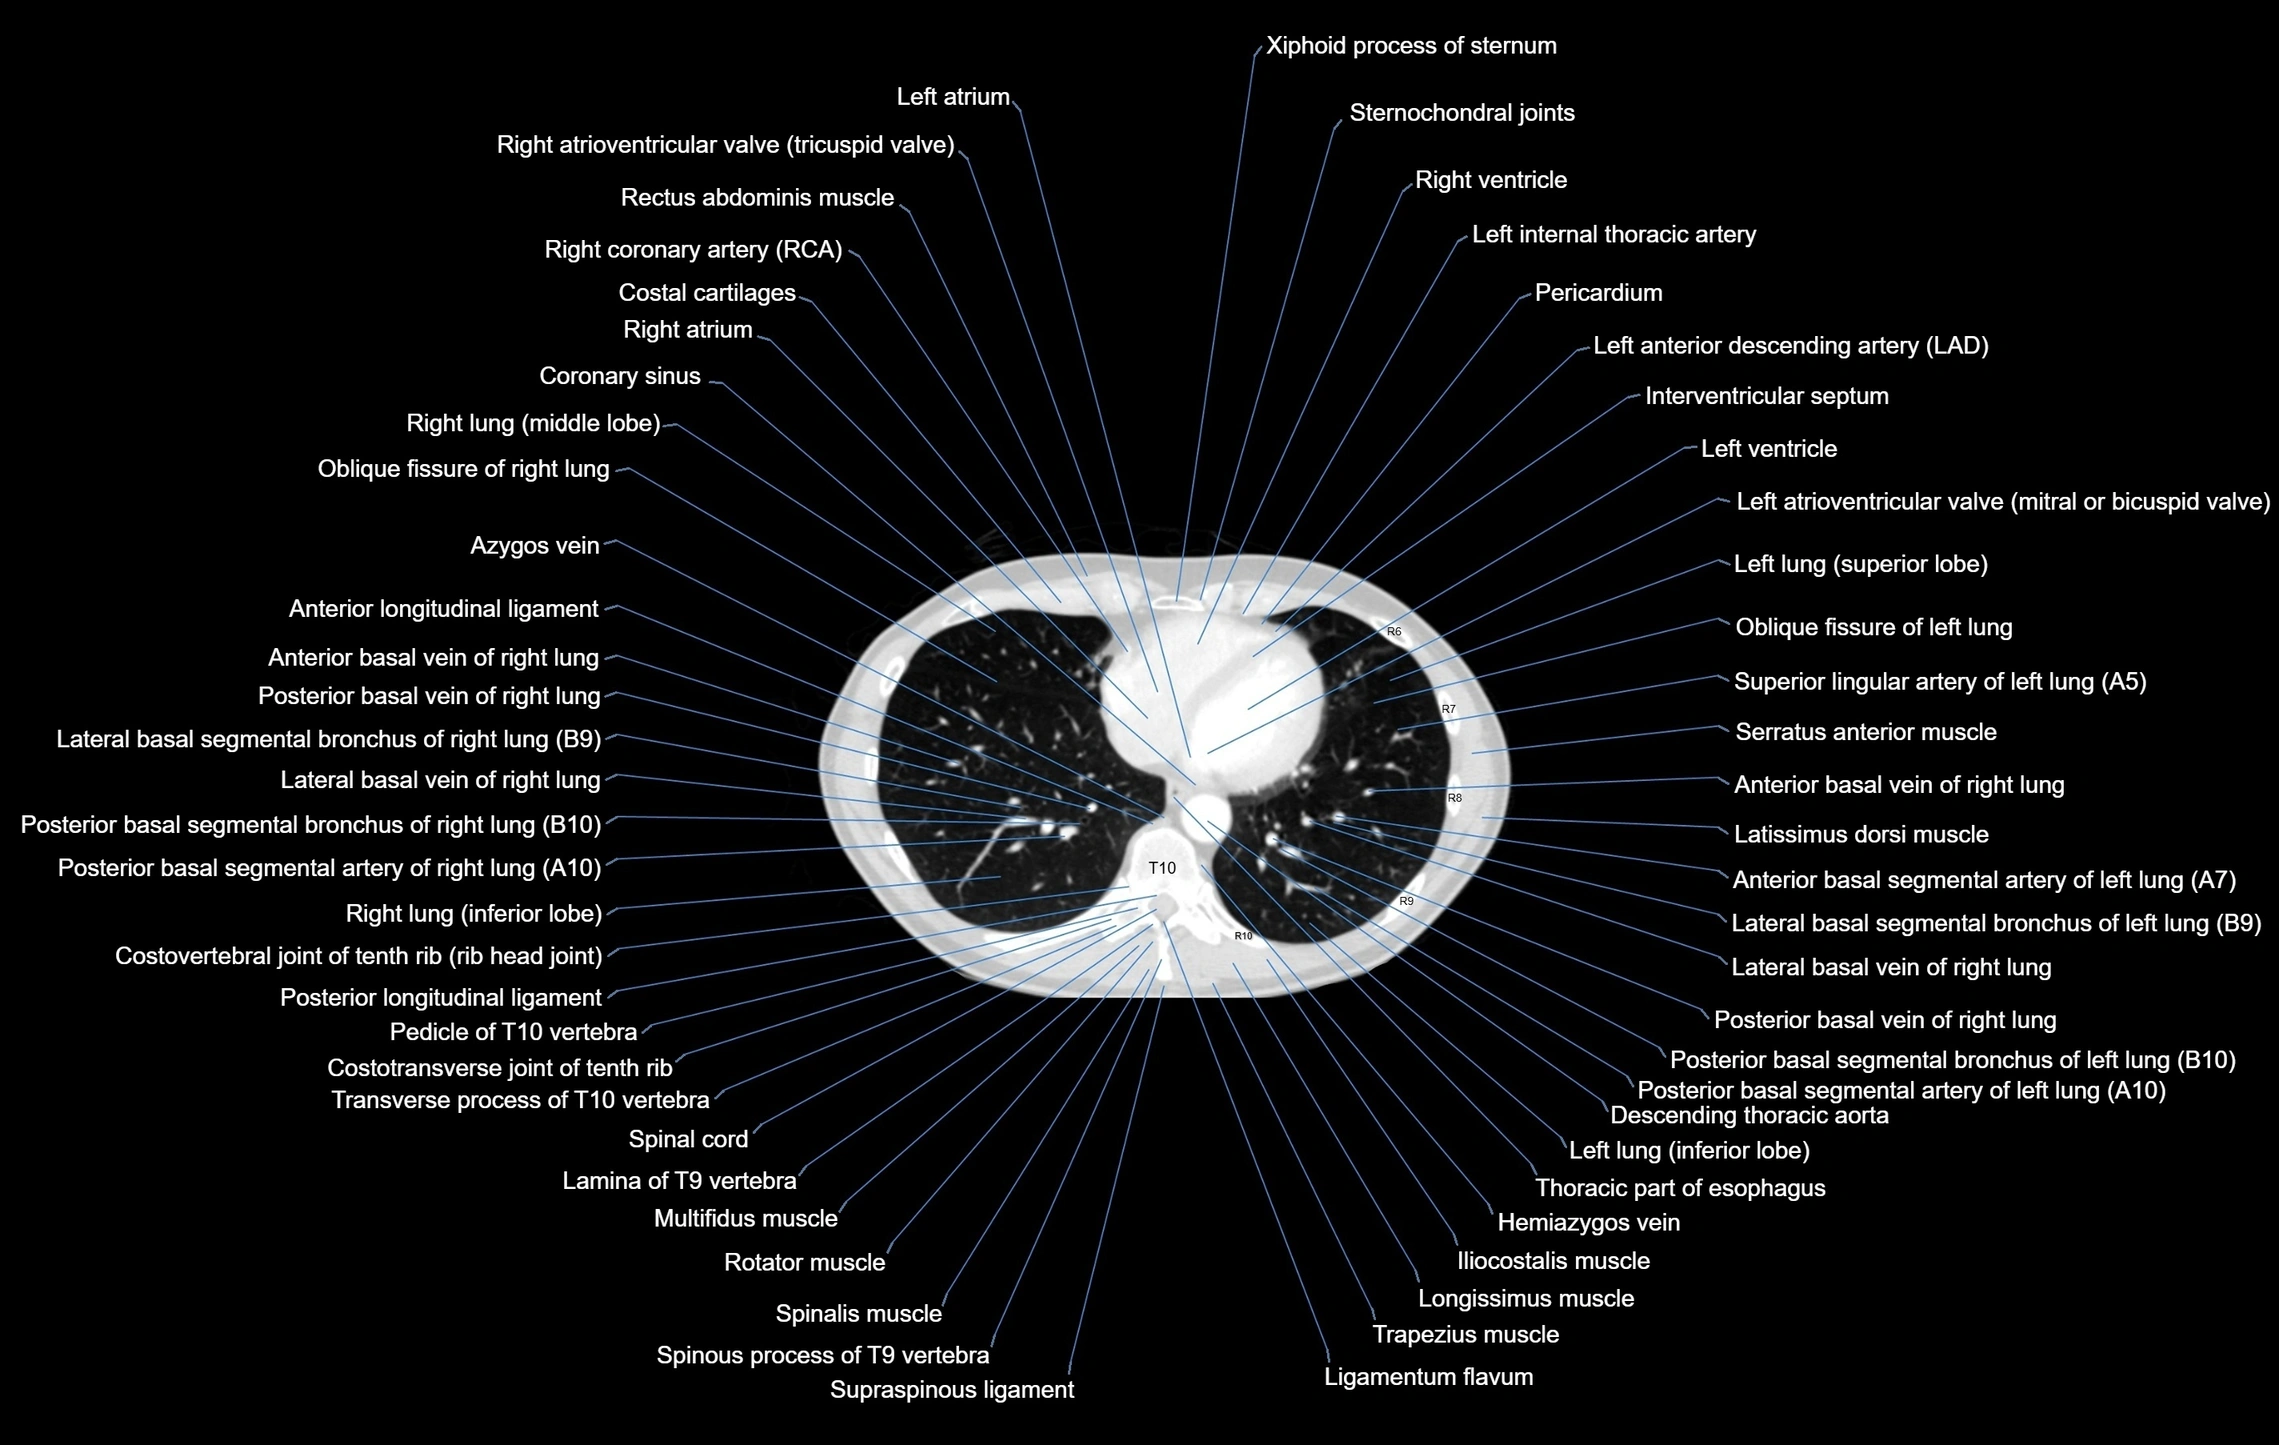

- Azygos vein

- Descending thoracic aorta

- Hemiazygos vein

- Posterior basal vein of right lung

- Posterior basal segmental bronchus of right lung (B10)

- Posterior basal segmental artery of right lung

- Lateral basal segmental bronchus of right lung (B9)

- Lateral basal vein of right lung